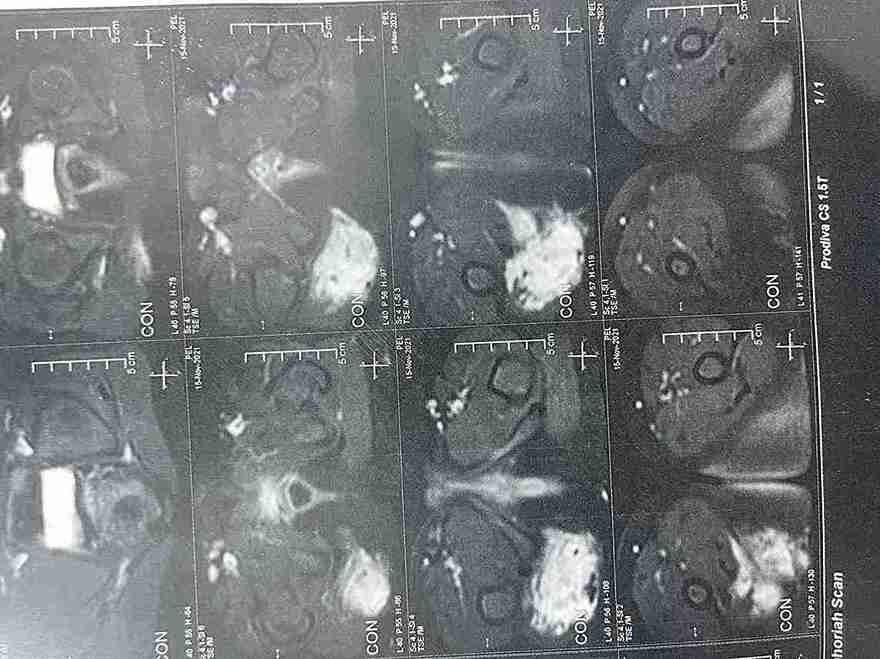

تم في هذه الحالة استئصال ورم حميد نادر (شوانوما) كان موجوداً على غلاف العصب الوركي (عرق النسا) الأيمن لطفلة تبلغ من العمر 5 سنوات ونصف. الورم كان يضغط على العصب مسبباً ألماً في منطقة الفخذ والأرداف. تمت الجراحة بنجاح تام مع الحفاظ الكامل على سلامة ووظيفة العصب.

• نتائج التحليل النسيجي أكدت أن الورم حميد (شوانوما).